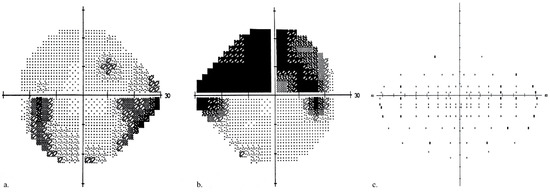

| Monocular VF | |||

| MD better eye (dB) | −5.848 ± 5.145 (−20.5–1.3) | 0.720 ± 0.948 (−1.42–2.18) | <0.001 |

| MD worse eye (dB) | −16.944 ± 8.224 (−32.4–6.4) | 0.292 ± 0.941 (−1.45–1.78 | <0.001 |

| Binocular VF | |||

| Defect scores (n) | 25.821 ± 18.387 (0–75) | 0.464 ± 0.999 (0–4) | <0.001 |

| Esterman coefficient score (%) | 78.482 ± 15.322 (37.5–100) | 99.613 ± 0.833 (96.6–100) | <0.001 |